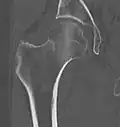

Intertrochanteric hip fracture in a 17-year-old male